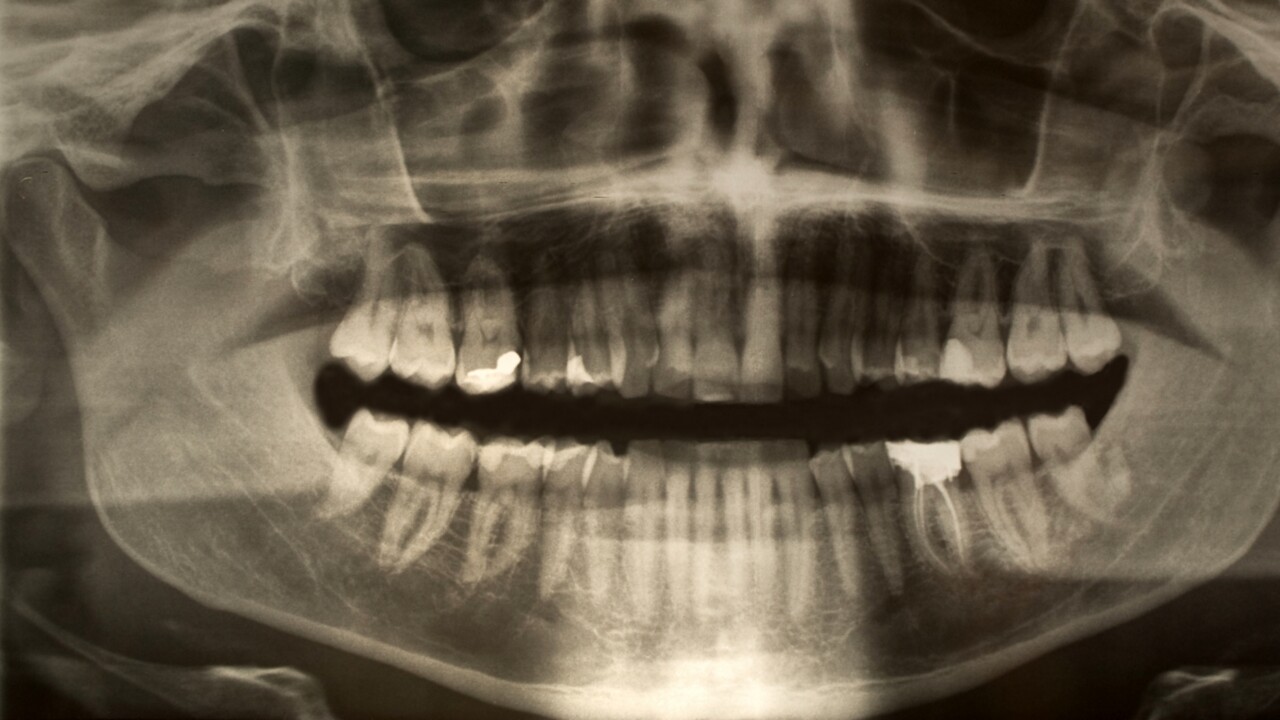

– Parodontit, eller tandlossningssjukdom, är en kronisk inflammation i munnen som från början orsakas av bakterier. Dessa bryter successivt ner de vävnader som håller tänderna på plats. På grund av denna inflammation orsakar våra egna osteoklaster i slutänden nedbrytning av käkben. Sjukdomen är utbredd världen över, särskilt bland äldre, och en av de största riskfaktorerna är bristande munhygien.

– När bakterier samlas runt tänderna ökar risken för att tandköttet blir inflammerat. Med tiden skapas en miljö som är både syrefri och rik på proteiner – perfekta förhållanden för vissa bakterier i munfloran att växa till och förvärra tillståndet.

– Vi studerar hur bakterier som är kopplade till parodontit kan sätta igång inflammatoriska processer i munnen. Fokus ligger både på hur bakterierna samverkar med varandra och på att identifiera genetiska markörer hos särskilt aggressiva bakteriestammar – något som i framtiden kan förbättra möjligheterna till tidig diagnos.

– Ett av våra mål är att hitta tillförlitliga markörer som gör det möjligt att med ett enkelt salivprov identifiera unga personer som bär på särskilt aggressiva bakteriestammar – och därmed löper ökad risk att utveckla parodontit i ett tidigt skede.